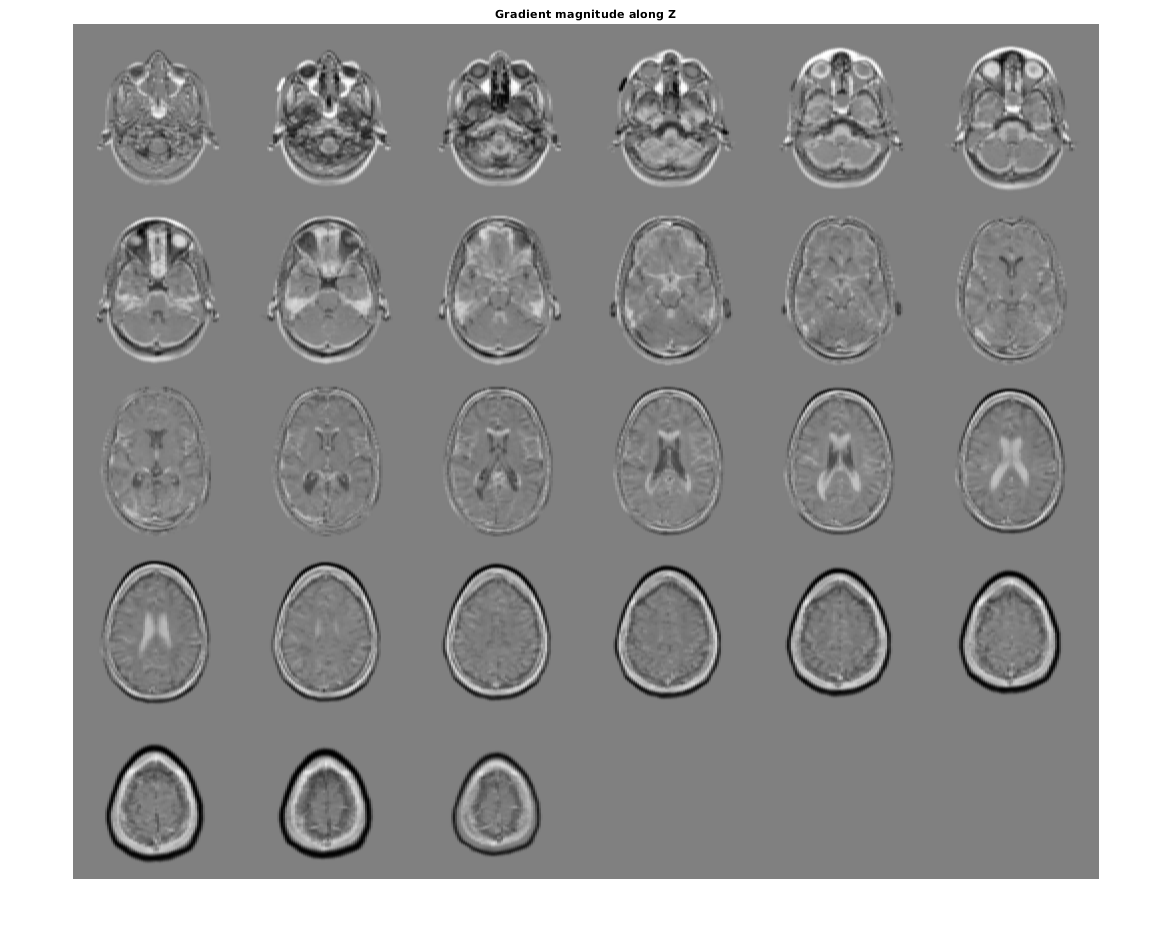

figure, montage(reshape(Gz,sz(1),sz(2),1,sz(3)),'DisplayRange',[])

title('Gradient magnitude along Z')